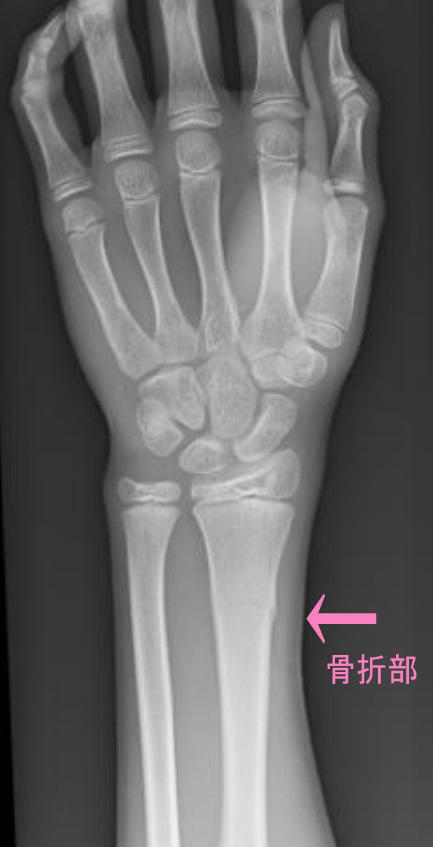

走っていて転倒し、手を突いたら骨折しちゃった・・・

とうこつ骨折.jpg